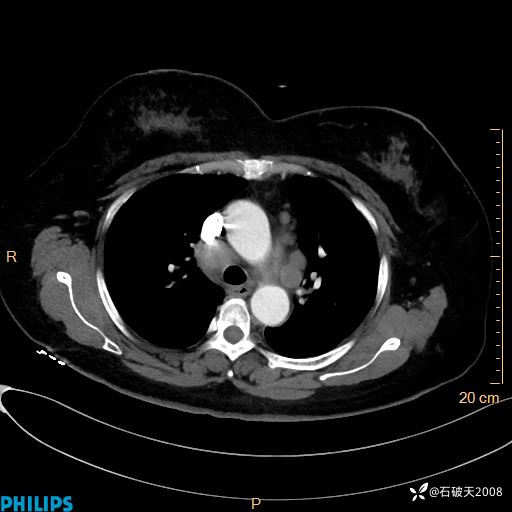

肺结节病?纵膈型肺癌?淋巴瘤?有点意思,欢迎围观

女 52岁 主 诉:咳嗽10余天,咳痰2天。

现病史:10余天前无明显诱因出现咳嗽,呈阵发性干咳,伴咽喉部发痒,无咽痛,无咳痰,无鼻塞、流涕、打喷嚏,无发热、畏寒、寒颤,无头痛、头晕,无胸闷、胸痛,无反酸、烧心,无腹痛、腹泻,无尿频、尿急,无皮疹等,在当地诊所求治,给予口服药物治疗(具体不详),病情无好转。遂在当地社区卫生服务中心开具口服药物治疗(具体不详),疗效欠佳。2天前出现咳痰,在我院门诊求治,行胸部CT提示肺部感染,建议住院,患者要求口服药物治疗,目前仍咳嗽、咳白色粘痰,白天量多,夜间自觉喉部喘鸣音,遂再次来院就诊,以“肺部感染”为诊断收入院。发病以来,神志清,精神可,饮食可,夜间睡眠差,大小便正常,近期体重无明显变化。

动脉期